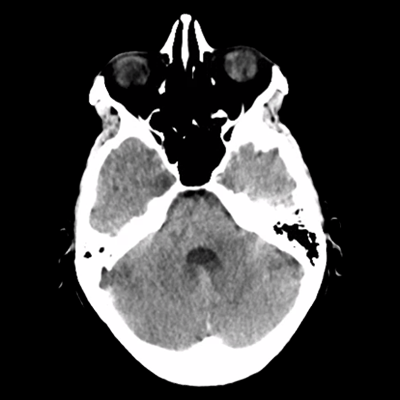

MRI sequences part 1 MRI sequences part 2 MRI sequences part 3

Her neuroimaging is clearly abnormal. Let's start with her MRI brain w/w/o contrast from one month ago. You can see the T2/FLAIR, T1 +C, and SWI sequences for three key slices. What do you notice?

She has some subtle FLAIR hyperintensities around the lining of her occipital horns. Minimal FLAIR hyperintensity in the right frontal region, though that's from her prior metastasis that was resected. What's notable is the absence of significant FLAIR hyperintensity around her right frontal lobe site, left frontal ependymal nodule, or even ventricular lining. There's no clear vasogenic edema or evidence of transependymal flow.

There's subtle contrast enhancement of the ventricles, shown here around the occipital horns and trigone, as well as of the ependymal nodule. What about the SWI sequences?

Other than the expected post-surgical changes, the left frontal ependymal nodule is hypointense. There's hypointense signal within the cerebellar foliae and fourth ventricle as well. While you'd normally think of subarachnoid hemorrhaging, in the context of her known metastatic melanoma, this all represents leptomeningeal spread of her cancer.